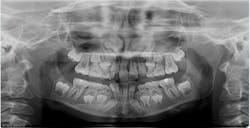

Can you see the supernumerary on this panoramic x-ray?

Panoramic images are often difficult to interpret due to significant superimposition; additionally, structures that are not centered in the focal trough are often not visualized or obscured beyond recognition. Additionally, even on the best panoramic, the exact location of the mesiodens cannot be determined.

Prior to starting Phase II, a Cone Beam CT with the i-CAT FLX QuickScan protocol was utilized. The 3D scan of the patient allowed for precise visualization of an inverted and impacted mesiodens located palatal to the central incisors that was difficult to see and was initially overlooked on the 2D panoramic image.